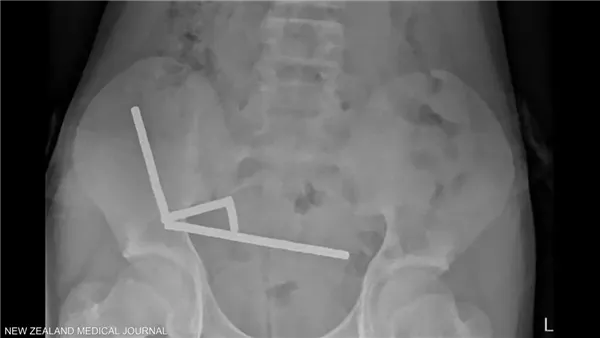

وأظهرت الأشعة أن المغناطيسات تكتلت معا في 4 خطوط مستقيمة داخل أمعاء المراهق، و"يبدو أنها كانت في أجزاء منفصلة من الأمعاء ملتصقة ببعضها البعض بسبب القوى المغناطيسية"، وفق الأطباء.

وأكد الأطباء أن ضغط المغناطيس تسبب في موت أنسجة في أجزاء من الأمعاء الدقيقة والغليظة.